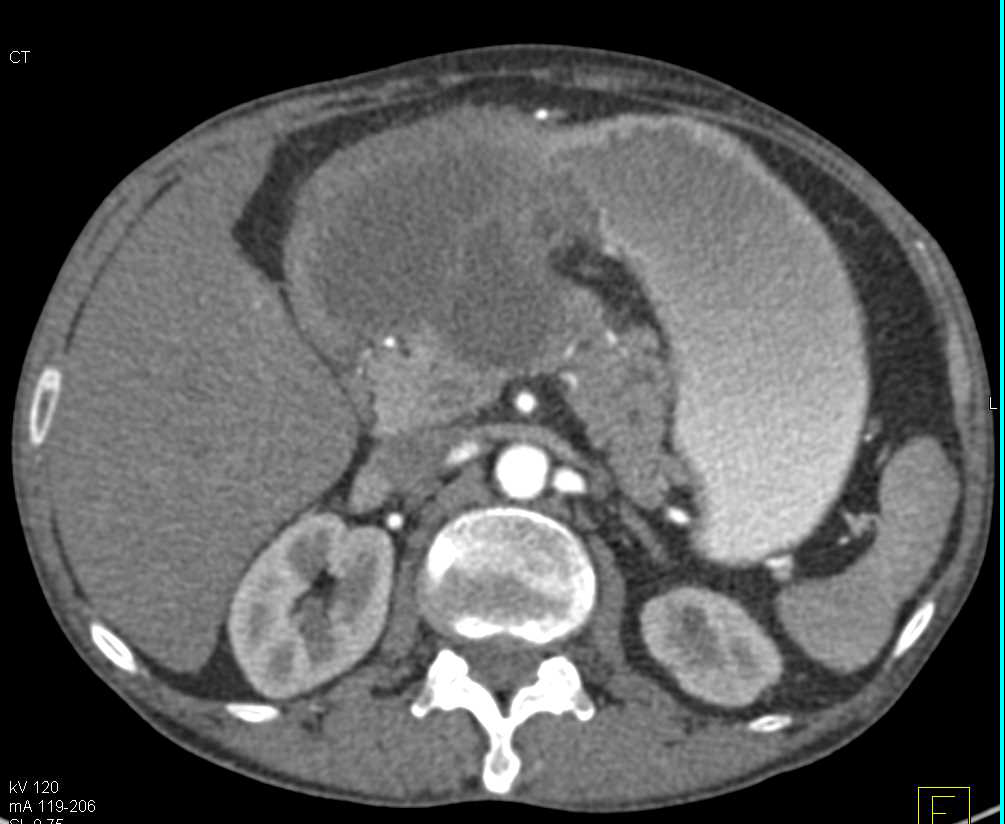

Retroperitoneal Neurosarcoma